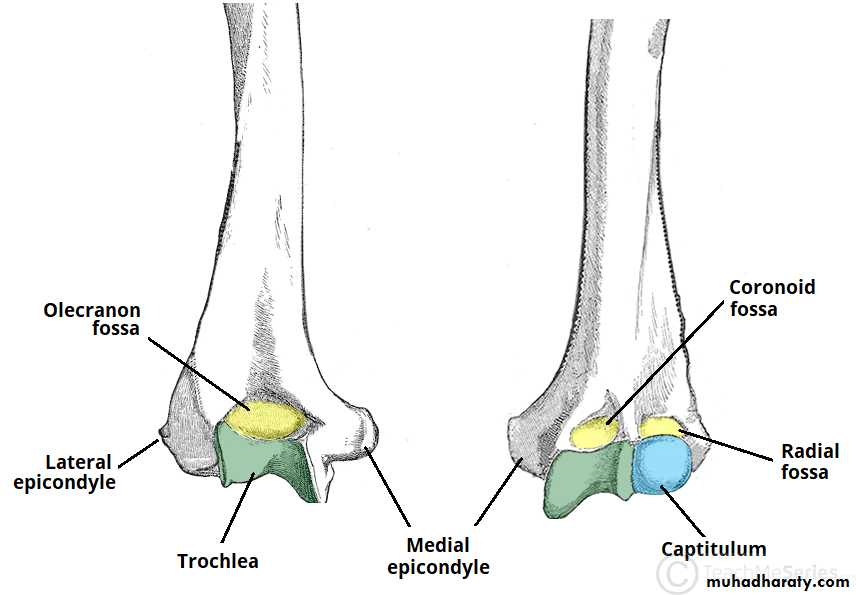

• عمليا يتم تصوير الرسغ والمرفق والكتف لمن يبدوا ظاهرا دون سن العشرين عاما من العمر. ويصور الحرقف لمن بدا في اواسط العقد الثالث من العمر او اقل, والنهاية الانسية للترقوة والتحام القص بالرهابة لمن تجاوز ذلك.

53• معدل ظهور والتحام المراكز التعظمية تبعا للعمر:

• 1) عند الولادة يظهر المركز التعظمي للنهاية السفلى للفخذ والمركز التعظمي لرأس عظم العضد.

• 3) في نهاية السنة الرابعة يظهر متع لرأس الكعبرة.

• 4) وفي بداية السنة الخامسة يظهر متع للعظم المربع المنحرف وفي نهاية السنة االخامسة يظهر المركز التعظمي لعظمي شبه المنحرف والزورقي الرسغيين.

• 5) في سن السادسة يظهر متع للقمة الانسية لعظم العضد والنهاية السفلية لعظم الزند.

546) في السنة الثامنة ونصف يظهر متع لبكرة العضد.

7) في نهاية السنة التاسعة يظهر متع للنتوء المرفقي لعظم الزند والعظم الحمصي.

8) في نهاية السنة العاشرة يظهر متع اللقمة الوحشية للعضد.

9) في سن 13 سنة وست شهور يظهر متع لعرف الحرقف.

10) في سن 15 سنة يظهر متع للنهاية الانسية لعظم الترقوة.

معدل التحام مراكز التعظم:

1) في سن 13-14 سنة تلتحم البكرة بعمد العضد.

2) في سن 14-15 يلتحم راس الكعبرة بالعمد والنتوء المرفقي بالزند.

3) في سن 16-17 سنة تلتحم اللقمة الانسية بعمد العضد.

4) في سن 17-18 تلتحم النهايتان السفليتان للكعبر والزند كل مع عمده.

5) في سن 18-19 يلتحم راس العضد بعمده.

6) وفي سن 25 سنة يلتحم عرف الحرقف بالحرقف والنهاية الانسية للترقوة بالترقوة.